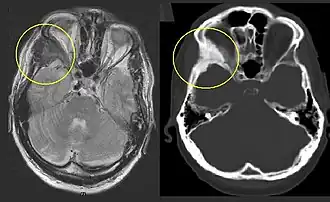

![]() Displasia fibrosa en el hueso cigomático, en comparación con el lado contralateral. | ||

Tomografía y resonancia magnética

Pueda ayudar evaluar con exactitud la magnitud de la afectación ósea. La intensidad de señal en la resonancia magnética es moderadamente baja en T1, mientras en T2 es alta o media. Con gadolinio, la mayoría de las lesiones muestra un incremento central de contraste y algunos anillos periféricos.[5] En general, la intensidad de la señal depende de la cantidad de trabéculas óseas, colágeno, quistes y hemorragias. El clásico aspecto en la tomografía es de «vidrio esmerilado», que corresponde al hueso sano que rodea a la lesión.[5]